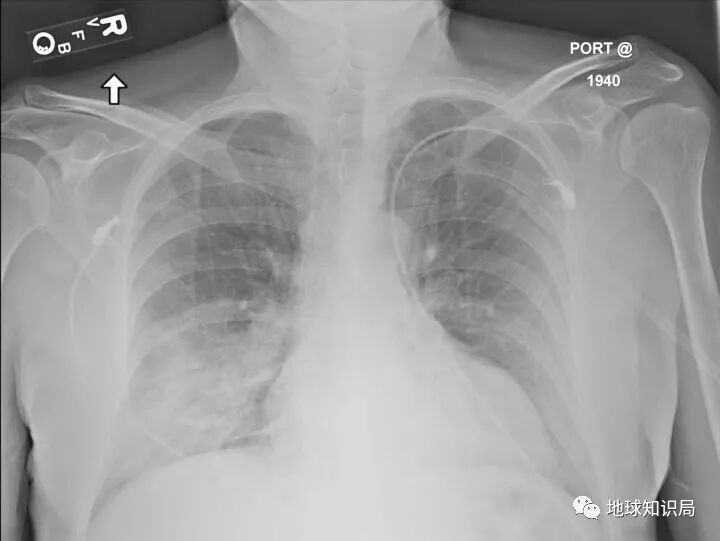

中东呼吸综合征患者的胸部X片

(图片来自:Wikipedia@US government employee)▼